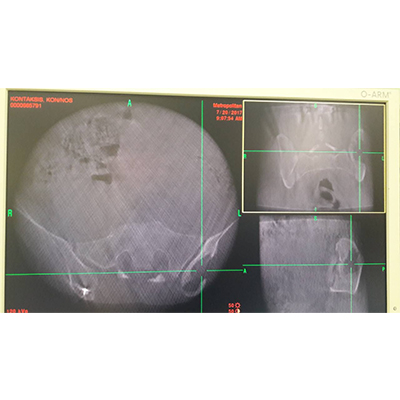

Διεγχειρητική τρισδιάστατη απεικόνιση σε πραγματικό χρόνο (ρομποτική χειρουργική), για την ασφαλή και ακριβή τοποθέτηση των χειρουργικών υλικών σπονδυλοδεσίας (α), αντιμετώπισης όγκου στον αυχένα - σπονδυλοσπλαστική (β, γ), και οστικής μετάστασης στη λεκάνη - θερμική εκτομή του όγκου με ραδιοσυχνότητες(δ)

Τέλος, η θεραπεία των οστικών μεταστάσεων στη σπονδυλική στήλη με την τεχνική της θερμικής εκτομής με ραδιοσυχνότητες είναι μια πρωτοποριακή τεχνική μικρής παρεμβατικότητας, που έρχεται να συμπληρώσει κενά ή αδυναμίες, τα οποία εμφανίζει η κλασική ακτινοθεραπευτική προσέγγιση. Μπορεί να εφαρμοσθεί σε όλους τους τύπους των οστικών μεταστάσεων, χωρίς τις πιθανές επιπλοκές της ακτινοθεραπείας (συστηματικές αιματολογικές επιπλοκές, μετακτινική μυελίτιδα ή δερματίτιδα κ.λπ). Εφαρμόζεται με διαδερμική τεχνική, για την οποία δεν απαιτείται γενική αναισθησία, ούτε χρειάζεται να διακόψει ο ασθενής προηγουμένως τη φαρμακευτική χημειοθεραπευτική του αγωγή. Αποτέλεσμα αυτού είναι η ταχεία ελάττωση του πόνου (95% των ασθενών αναφέρουν σημαντική ανακούφιση, ήδη από τη δεύτερη εβδομάδα, καθώς και σημαντική μείωση στη χρήση οπιοειδών αναλγητικών), ενώ έχει βρεθεί και σημαντική μείωση στην πιθανότητα επέκτασης της μεταστατικής νόσου. Φυσικά, η θερμική εκτομή του μεταστατικού όγκου μπορεί να συνδυασθεί και με άλλες ελάχιστα επεμβατικές χειρουργικές τεχνικές, όπως κυφοπλαστική ή διαδερμική σπονδυλοδεσία, όποτε υπάρχει ανάγκη.